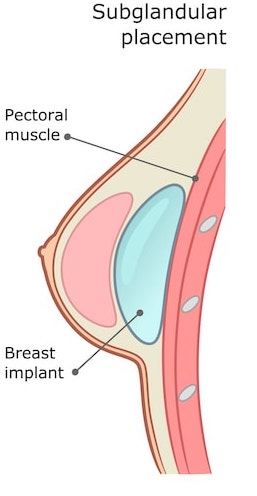

Subglandular

Subglandular implants refer to implants that are placed underneath the breast tissue, but on top of the pectoral muscle. This is “over the muscle” placement. The rationale behind an over-the-muscle placement is that it involves less interference and can create a more teardrop-shaped result for some women, while avoiding the risk of animation or visible distortion when activating the chest muscles. There are a number of pros and cons of over the muscle implants:

- Patients see less animation during physical activity with over-the-muscle implants, as the pectoral muscle is not impacting the movement of the breast implant

- There is less discomfort during recovery, and recovery is often considered easier with over-the-muscle implants due to the lack of muscle interference during surgery

- Over the muscle implants can produce a very natural result for women with existing breast tissue.

- There is a higher risk of implant visibility in patients with a subglandular placement, particularly with patients that have less breast tissue or poor skin integrity

- Over the muscle placement can impact mammogram views slightly.

- Over the muscle placement may increase capsular contracture risk.

Subglandular (over-the-muscle) placement is more appropriate for patients that have existing breast tissue that will cover the implant edges. Over the muscle is particularly recommended for patients that are bodybuilders or train upper body regularly, as there is less animation of the breasts during workouts with a subglandular placement.